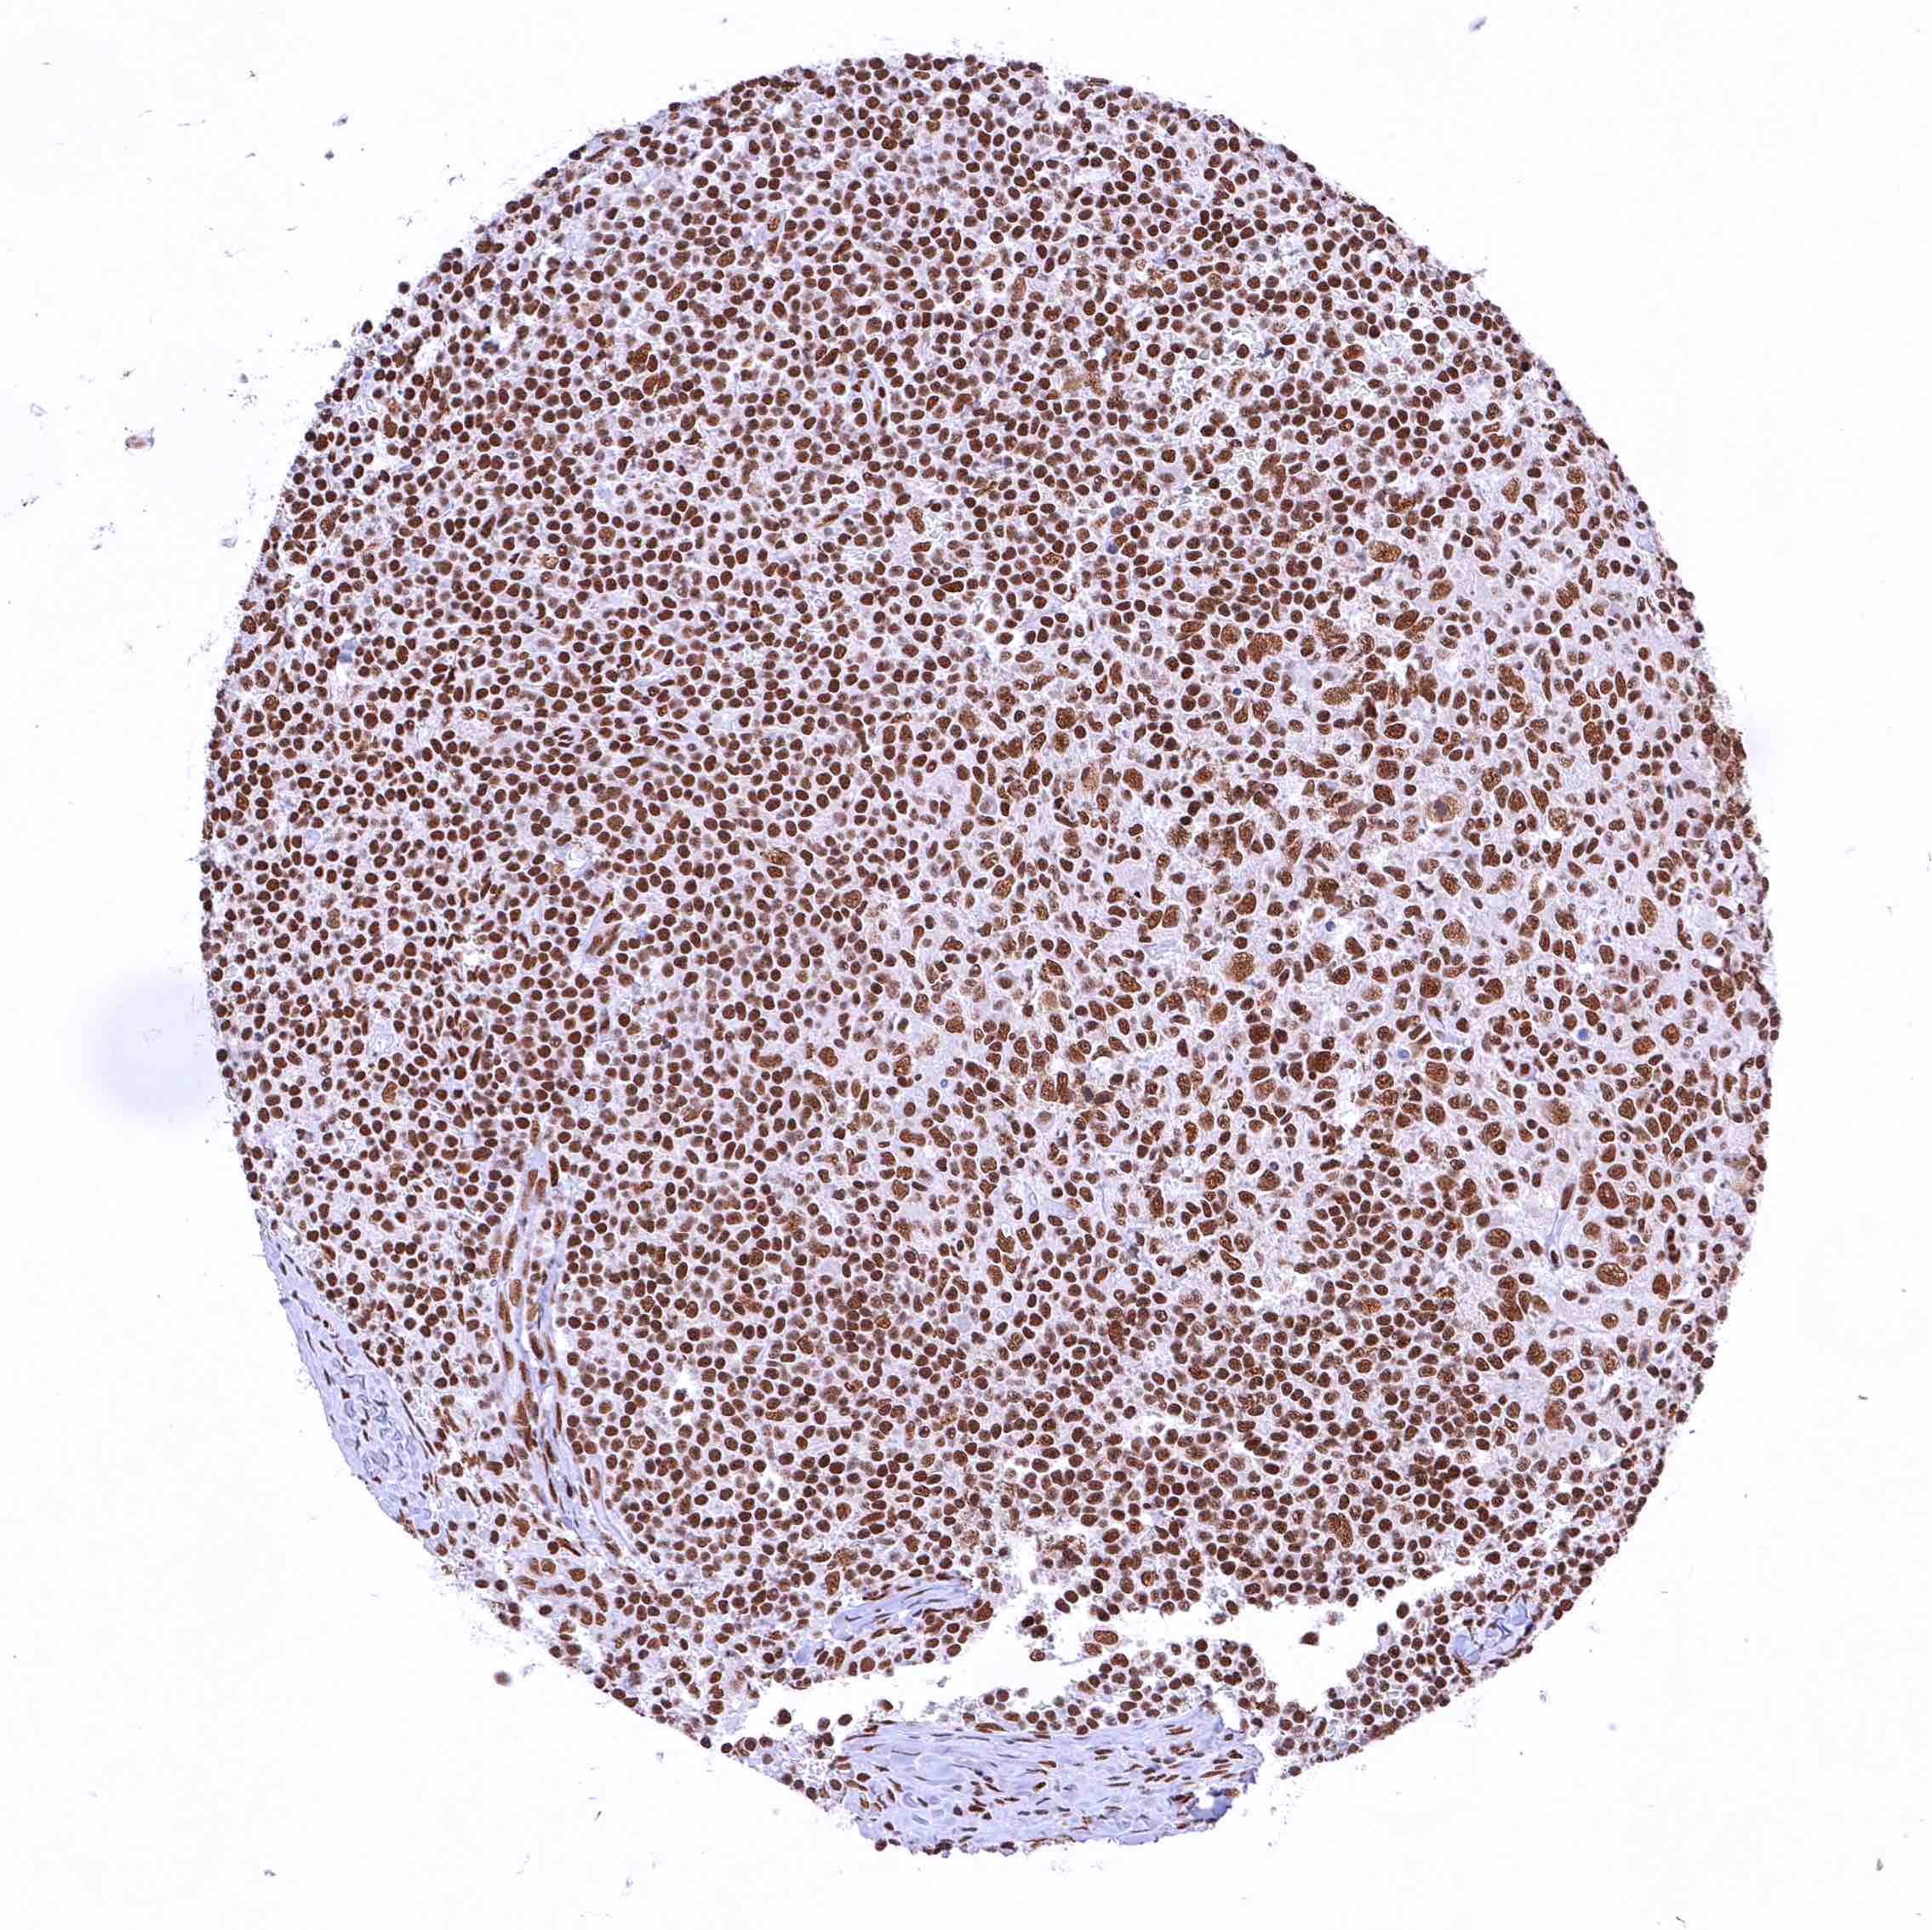

Thymus